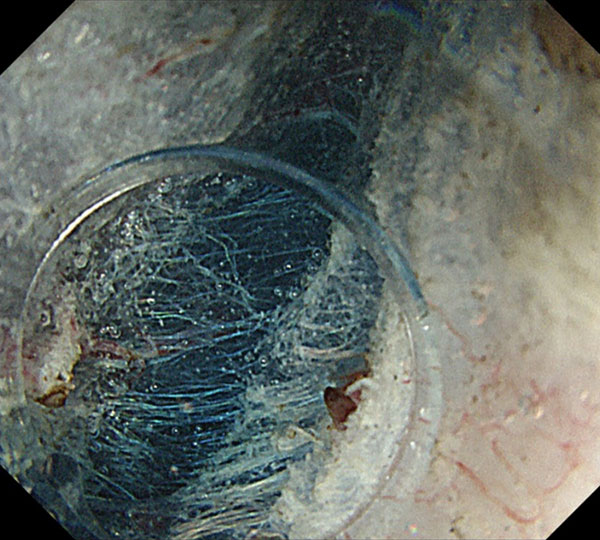

ESDの手法としては、浸水下ポケットクリエーション法を主体に行っています。脱気した状態で行うため、患者さんも楽に受けられ、筋層直上で安定して切除できるため、繊維化がある病変の切除も容易です。切除された標本の状態も良好で、正確な病理学的評価が可能です。

5. 内視鏡先端が挿入できるほど剥離が進むと、内視鏡が安定し、粘膜下層を直視しながら筋層直上のラインで正確な剥離操作が可能となります。粘膜下層に軽度の線維化を認めますが、この程度の線維化は剥離には全く問題ありません。周囲粘膜を切開していないため剥離が終了するまで粘膜下層の良好な膨隆が得られます。